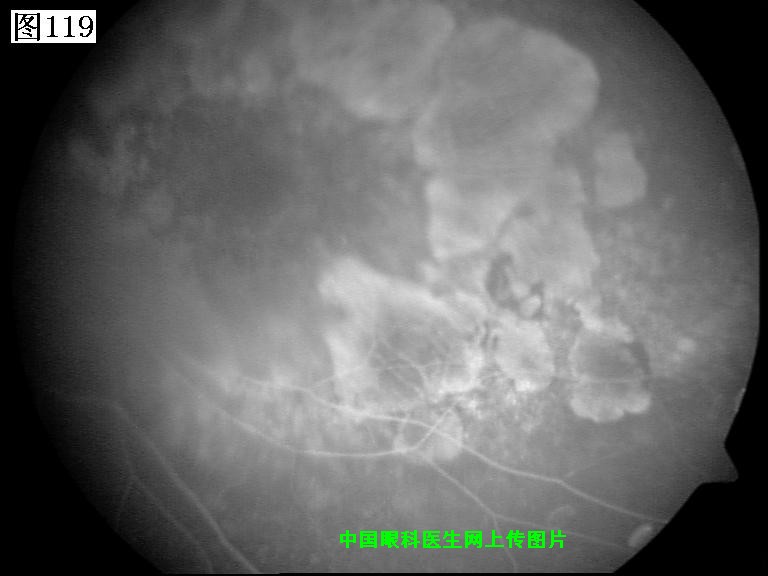

117 118 119 120